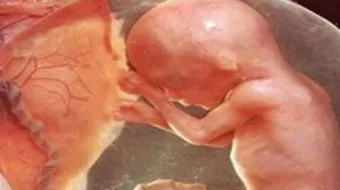

كيف يتكون الجنين في الشهر الرابع

- يصل طول الجنين في هذا الشهر حوالي خمسة عشر سنتيمتراً، أمّا بالنسبه لوزنه فيصل إلى ما يقارب المئة وعشرين جراماً، حيث يكون حجم الجنين بحجم قبضة الكف في بداية الشهر ويصبح بحجم الكف عند نهايته.

- تتكامل أجزاؤه وأعضاؤه ويمكن تمييزها بعضها عن بعض، كما يمكن تمييز بصمات أصابعه في هذه المرحلة.

- يبدأ شعر الجنين بالتكوّن حيث يغطي الشعر الرأس في البداية، ثمّ يتكون كلٌّ من: الحاجبين والرموش، كما أنّ الجلد يبدأ بالتكوّن.

- يبدأ النشاط العصبيّ الموجود في الدماغ بالنمو، ويستقر عمل القلب وينمو الجهاز الدوري بشكلٍ تدريجي، وفي منتصف هذا الشهر بالتحديد يمكن سماع نبضات الجنين من خلال أشعةٍ تعرف باسم أشعة الدوبلر، ويُلاحظ حدوث تباطؤ في نبضات القلب مقارنةً بالثلث الأول من الحمل حيث تتراوح في هذا الشهر بين المئة وعشرين وحتى المئة وستين نبضةً.

- تظهر حركاتٌ انعكاسيةٌ في كلٍ من الذراعين والساقين.

- يبدأ الطفل بمصّ إبهامه بالإضافة إلى اللعب بالحبل السري، وتشعر الأم بحركته في أحشائها.

- تنمو عظام الطفل وتزداد قوتها وطوالها.

بالإضافة إلى كل ما سبق يمكن معرفة جنس المولود سواءً كان ذكراً أم أنثى.